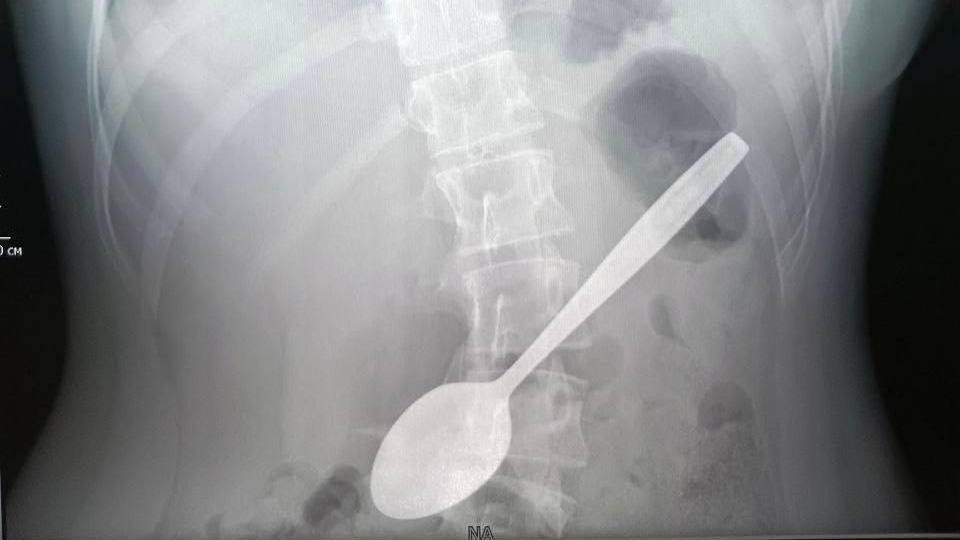

Подмосковные врачи достали из желудка школьницы 15-сантиметровую ложку

Фото: Минздрав Московской области / Telegram

Врачи Детского клинического центра имени Л. М. Рошаля извлекли из желудка девочки ложку длиной 15 сантиметров, которой она пыталась достать застрявший в горле кусок яблока. Об этом в понедельник, 5 мая, рассказали в Минздраве Московской области.

В ведомстве отметили, что длительное нахождение металлического предмета в желудке может вызвать серьезные осложнения, такие как пролежень, перфорация стенки или непроходимость, но в данном случае ложка не успела причинить вреда.

Сообщается, что операция длилась около часа и прошла успешно. Сейчас девочка чувствует себя хорошо и уже выписана домой.

— Юная леди пыталась ею достать кусок яблока, который застрял у нее в горле, и случайно проглотила, — передает Telegram-канал министерства.